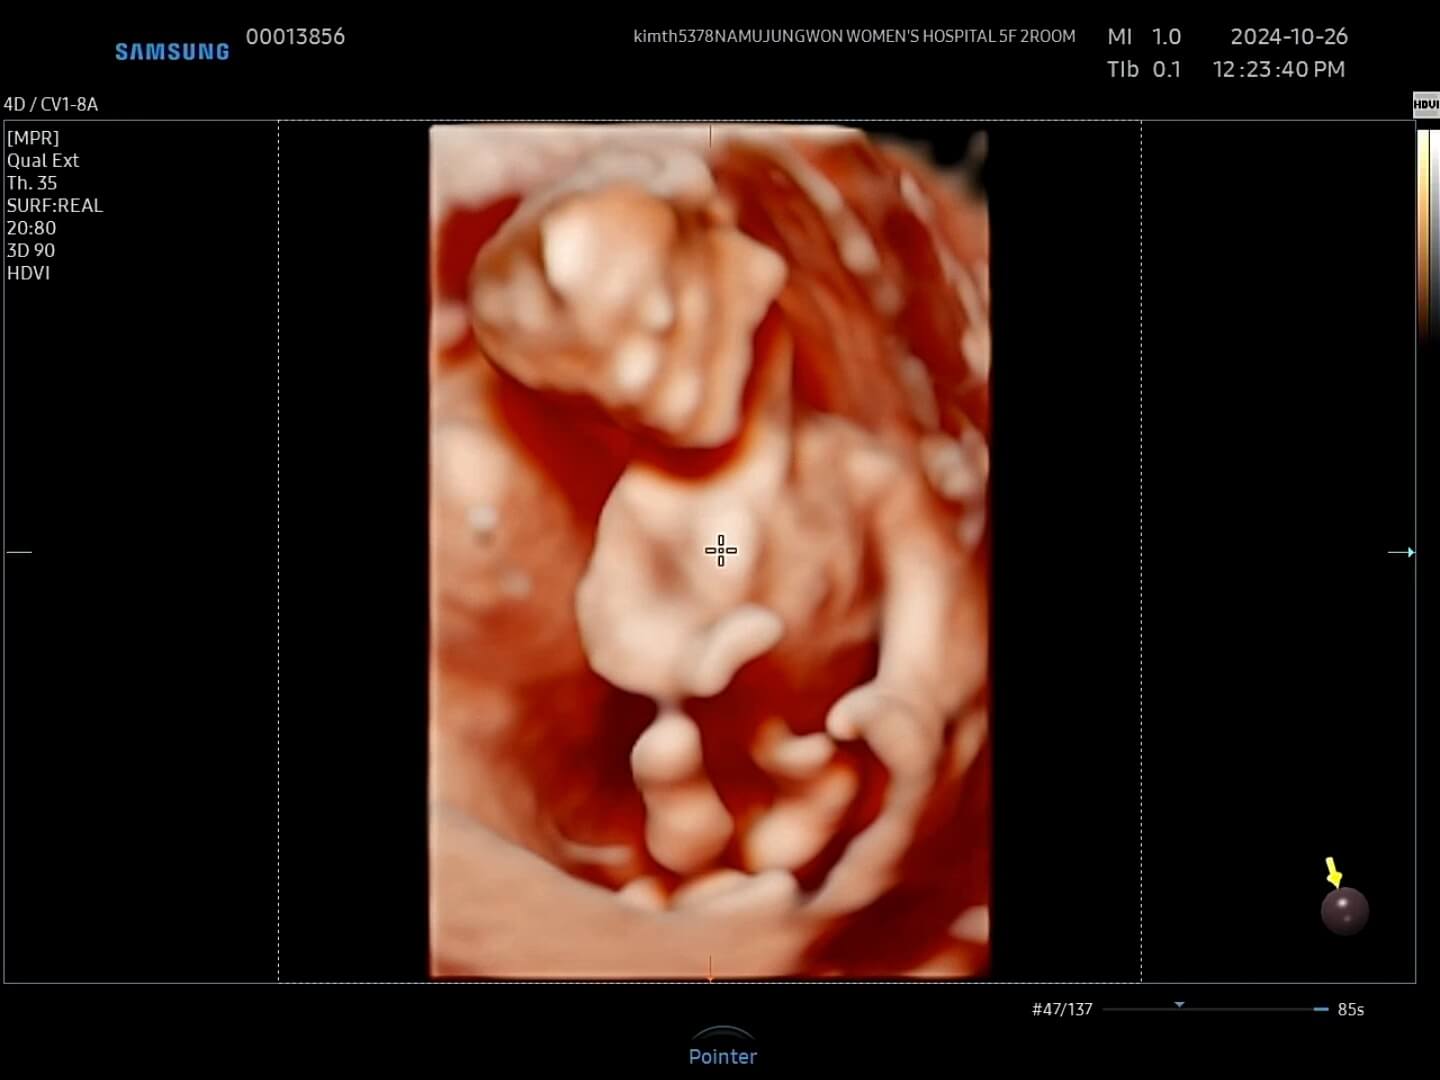

12주-입체초음파 12주에는 첫 입체초음파를 보게 되면서 팔, 다리가 잘 형성되었는지 정도를 보는 것 같아요. 12주부터 '태아'라고 부르기도 한답니다. 우리 꾸미는 처음에는 등을 돌리고 있다가 서서히 얼굴을 보여줬습니다. 벌써부터 귀여워요! 아들인지 딸인지 너무 궁금했는데요, 성별은 입체 초음파가 아닌 일반 초음파로 봐야한다고 하셨어요.

이제 일반 초음파로 목투명대와 코뼈가 잘 형성되었는지 확인합니다. 목투명대는 이물질이 쌓이는 공간이라고 보시면 되고, 이 목투명대가 2.5~3mm 정도 이상되면 기형아 확률이 높아지기에 이때, 융모막 검사나 니프티 검사를 실시하게 됩니다.

목투명대-코뼈 꾸미 목투명대는 다행이 1mm로 통과하였고, 오른쪽 사진을 보시면 얼굴 쪽에 하얀색깔 뼈가 있는데 이게 코뼈라고 하시더라구요. 이 코뼈도 잘 형성되어 있어서 눈으로 확인해주시는 1차적인 검사는 통과했어요. 그리고 나서 피를 뽑았는데요. 12주에 1차 기형아 검사로 피를 뽑고, 16주쯤에 2차 기형아 검사로 피를 또 뽑는데, 이 두 시기에 뽑은 피를 검사해서 최종적으로 기형아 검사 '저위험군'인지 '고위험군'인지 확인이 됩니다. 꾸미는 목투명대와 코뼈가 잘 보여서 일반 기형아검사를 실시하였습니다.

아, 그리고 성별은 원장님께서 80% '블루'라고 보시면 될 것 같아요. 라고 말씀해주셨는데 과연 반전이 일어날까요?